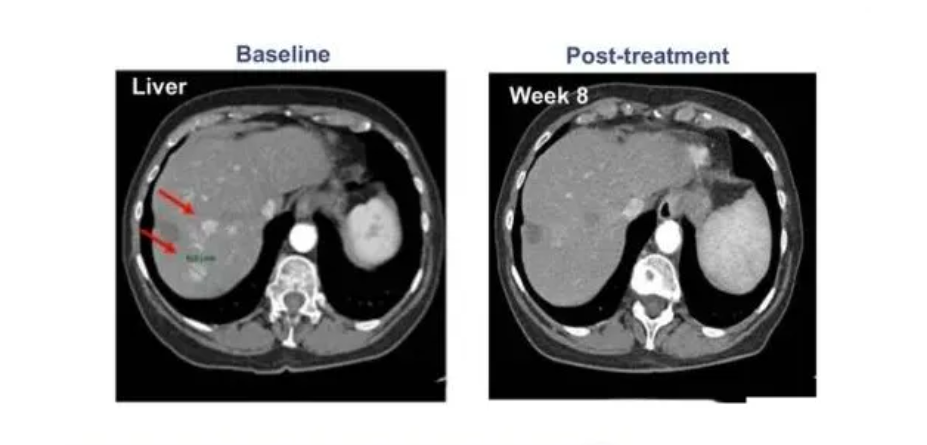

此前,在2020年國際肝病大會(ILC)上,一款基于T細胞的肝癌新型TCR-T療法ADP-A2AFP引起了不小的轟動,在納入的患者中,有一名患者的癌細胞進程出現(xiàn)了完全緩解,其余參與者的甲胎蛋白(AFP)也都出現(xiàn)了不同程度的下降,這意味著試驗取得了進展,也說明該療法針對晚期肝癌的治療是有效果的。